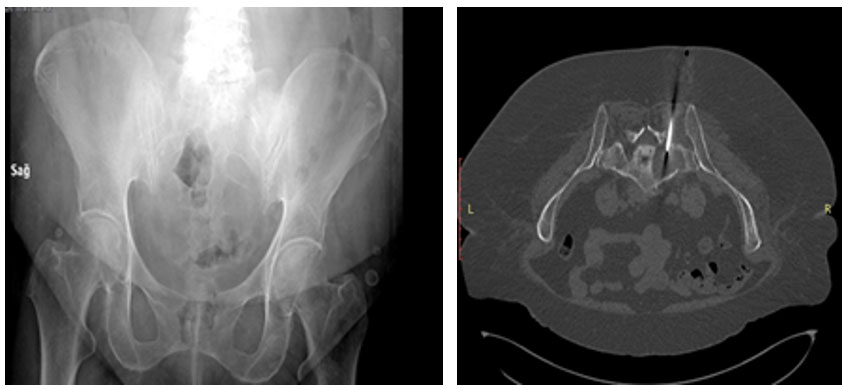

Ameliyat Öncesi: Röntgende sakrum sağ tarafta yeniklik, Tomografide tümör içinde iğne biyopsisi görülmekte